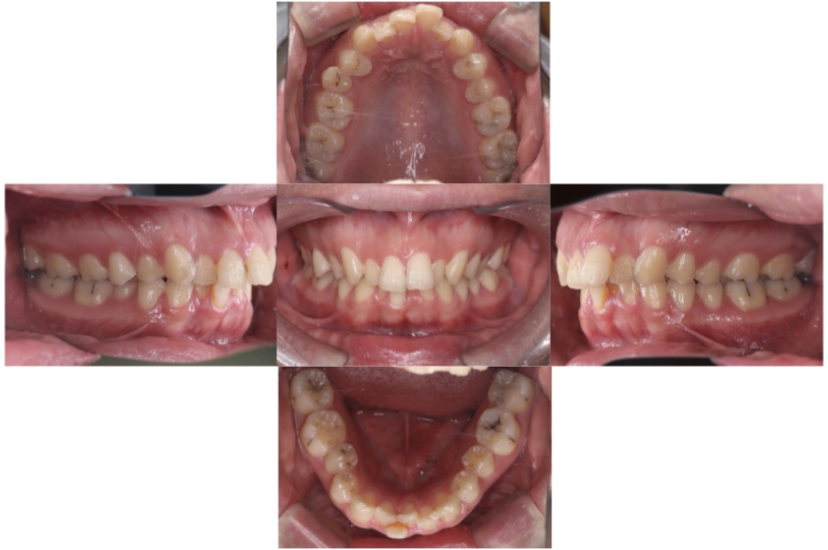

BEFORE

AFTER

症例3

叢生

抜歯

ブラケット矯正

上下顎叢生(上下の前歯のガタガタ)のケースです。

装置はラビアル(上下表側)で、上下顎の小臼歯を4本抜歯を行っています。抜歯したスペースを使って、上下の前歯の後方移動と叢生(ガタガタ)の改善を行っています。

主訴 八重歯を治したい。

年齢・性別 25歳 女性

お住まいの地域 神奈川県川崎市

治療方針 抜歯スペースを利用して上前歯の叢生(ガタガタ)の改善

抜歯部位 上下顎左右第一小臼歯

使用装置 ラビアル(上下表側)、顎間ゴム

治療期間 1年11か月

治療回数 16回

リテーナー クリアリテーナー